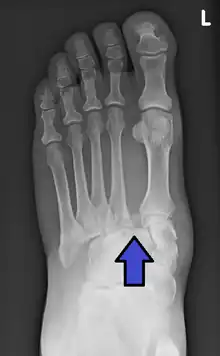

The Lisfranc ligament is injured or disrupted in the Lisfranc fracture. Trauma to the midfoot is caused by direct and indirect impact forces. Direct force involves an object landing on the surface on the foot. Indirect force involves twisting of the foot, usually an impact to the heel while the foot is pointed down toward the ground.[4] A mild form of this injury results in a widening of the gap between the first and second metatarsals. An extreme form of the a Lisfranc fracture causes a complete dislocation of the metatarsals from the tarsal bones. When the alignment of the midfoot is affected joint cartilage is quickly damaged.[5]